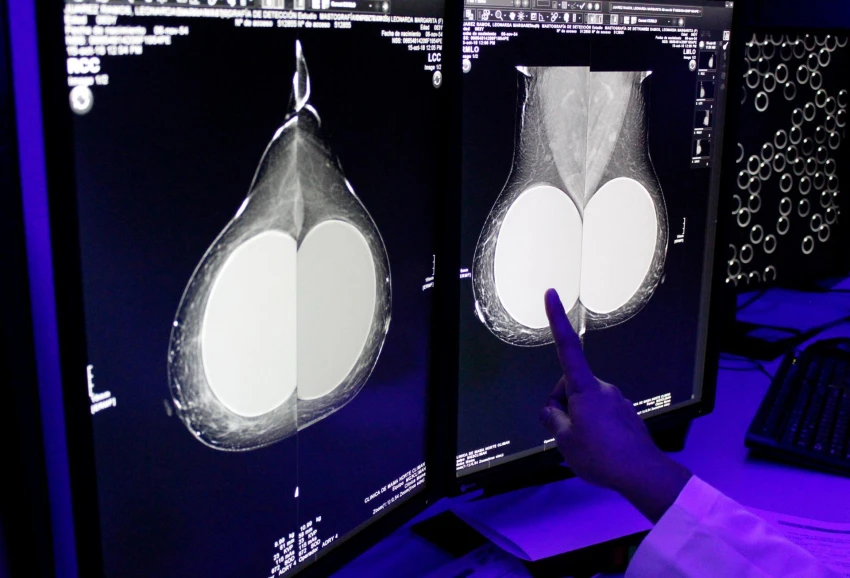

©Cuartoscuro - El cáncer de mama puede ser intervenido a tiempo con la oportuna detección.

Una autoexploración no sustituye una mastografía

Conocer tu cuerpo y detectar anomalías tempranas puede salvar tu vida, y a pesar de que la autoexploración no sustituye una mastografía, es una práctica esencial que te permite identificar posibles signos del cáncer de mama y buscar atención médica a tiempo.